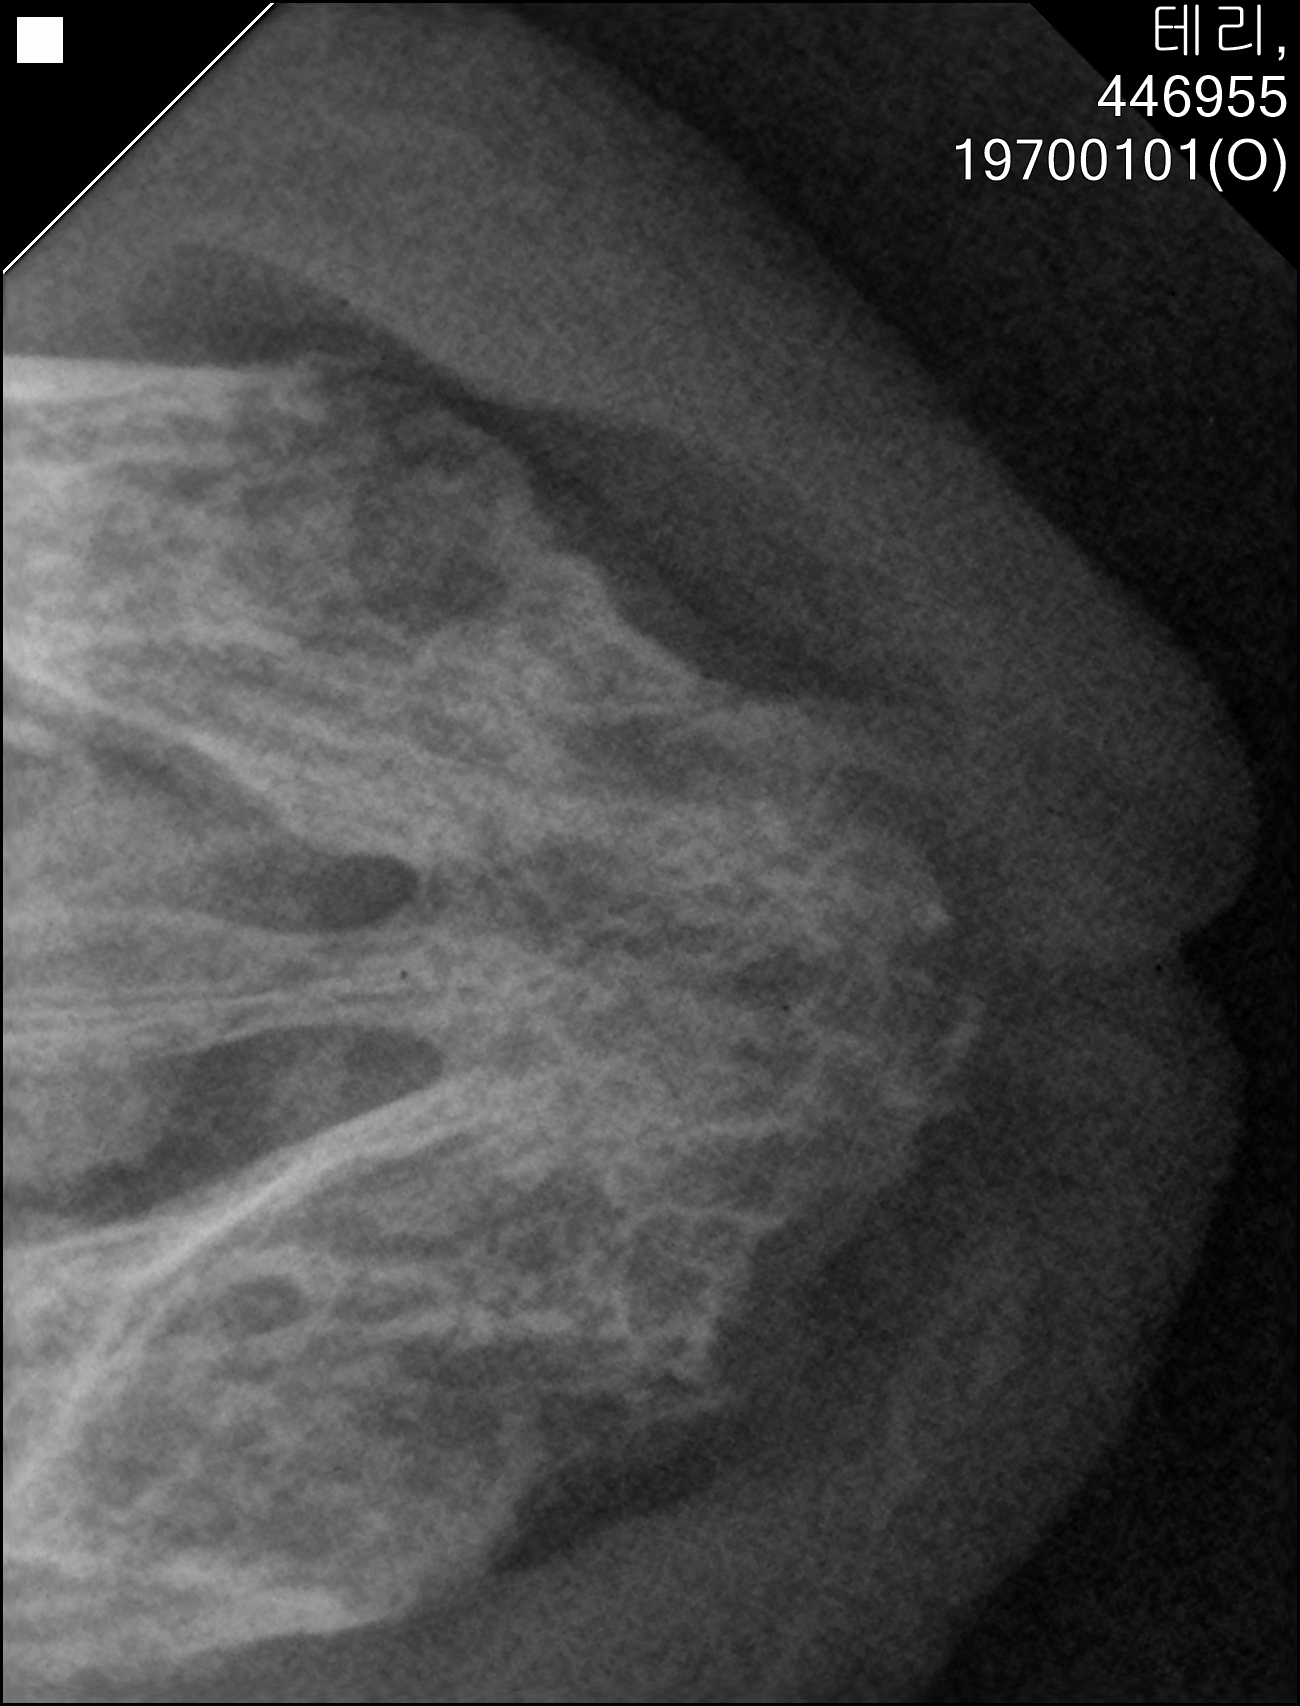

| 대상묘신청당시상태 | 작년 1월쯤 카오스 고양이는 제가 만들어 놓은 급식소에 밥을 먹으러 왔을 때 처음 본 냥이었어요. 작년에는 제가 일을 다녔기에 밤에 퇴근하고 집에 아이들 케어하고 난 뒤에 급식소에 나갈 수있었기에 늦은 밤 또는 새벽에 주로 다녀서 당시에는 카오스냥이의 상태를 알 수가 없었지만 누군가 급식기 바닥과 사료에 침을 묻혀놓은것을 확인하고 약밥을 챙겨가서 확인한바 카오스냥이가 혀바닥을 내밀고 있는것을 확인한 뒤 챙겼습니다. 제가 사는 동네가 아니어서 매일 많은 급식소를 챙길수는 없어도 급식소와 큰 급식기를 구비해 놓아서 이틀에 한 번씩은 가서 밥을 채우며 카오스냥이도 약밥을 챙겨주었어요. 그러다가 올해 2월이 되자 저는 퇴사를 했고 허리와 양쪽무릎 큰 수술 3가지를 하기 위해 병원에 입원을 했고 아이들 급식소는 지인께 부탁드려서 7월까지 사료와 물만 채워 주었습니다. 그러다가 올해 8월부터 제가 급식소에 나가게 되었고 예전에 제가 늦은밤에 다닌터라 아이들도 그 루틴에 맞춰서 제 차 소리가 나면 나타나거나 시간대에 와서 기다리곤 했는데 카오스냥이를 다시 본 것이 제가 급식소에 나가면서 8월 초쯤 카오스냥이를 보았습니다. 급식소에 있는 급식기 바닥에 침이 있고 사료에도 침이 묻은 알갱이가 있는것을 확인후 카오스냥이란걸 알게 되었어요. 제가 수술받고 재활하는동안 아이의 구내염은 더 진행이 된듯 털은 엉켜서 엉망이었고 많이 야윈상태여서 더는 약밥으로 저아이의 구내염을 관리하는것이 힘들다 판단하여 고보협에 신청하기도 전에 혹시나 하고 설치한 포획틀에 잡혔습니다. |

| 치료전 대상묘 사진 | ![]() |

구조전 태리입니다.